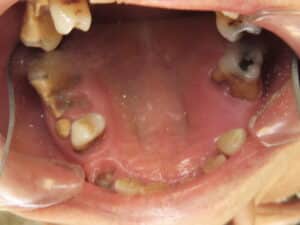

IMG 0953